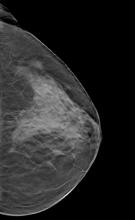

Breast Imaging | May 08, 2023

In addition to women with dense breasts, there are also other women for whom mammographic screening is not really enough, which is why research needs to continue in this field. Dr. Wendie Berg, a leading breast cancer specialist, talks with ITN about new research and advancements in breast imaging technology.

Dr. Berg, MD, PhD, FACR, FSBI, is Professor of Radiology at the University of Pittsburgh School of Medicine and Magee-Womens Hospital of UPMC, specializing in breast imaging. She is also the Chief Scientific Advisor to DenseBreast-info.org. A renowned expert, she writes and co-edits one of the leading textbooks on the topic, Diagnostic Imaging: Breast, currently in its third edition, and has co-authored over 120 peer-reviewed research publications.